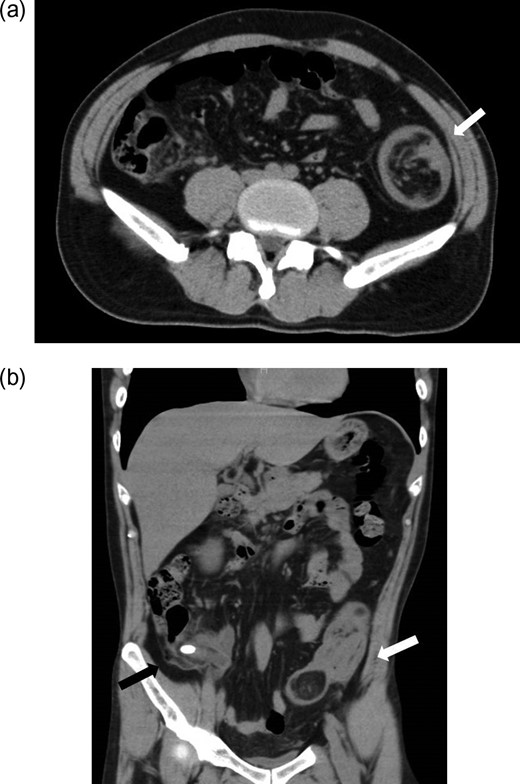

While awaiting surgery, the patient developed sudden-onset lower abdominal pain and was readmitted. On physical examination, the abdomen was distended with right lower quadrant tenderness to palpation and rebound tenderness. Laboratory data revealed elevation of the white blood cell count to 18 000/mm3 and a serum C-reactive protein level of 5.8. Antegrade colo-colonic intussusception was observed on CT with the lipoma of the descending colon as the lead point (Fig. 3a, b). The appendix was acutely inflamed, and calcification was seen in the appendix with inflammatory changes in surrounding tissues (Fig. 3b).

CT findings at the time of readmission: CT of the abdomen at readmission (a: axial view, b: coronal view) demonstrated antegrade colo-colonic intussusception with the lipoma in the descending colon as the lead point (white arrow). The appendix was also found to be swollen with a high density mass suspected to be a fecalith in the lumen, with inflammation in surrounding tissues (b, black arrow).